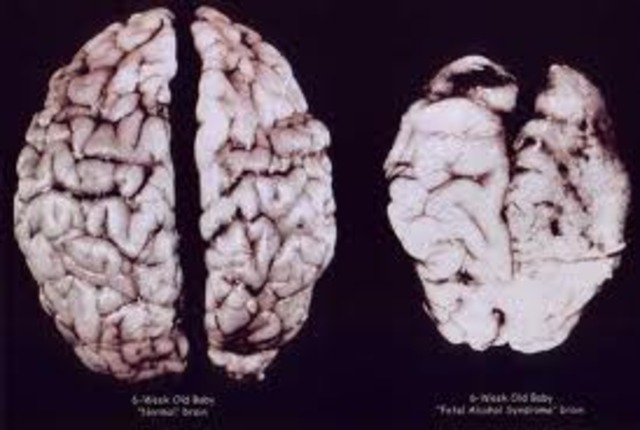

There is a high risk for brain damage when the baby is born before 26 weeks.

By 9-10 weeks the brain is still not controlling the fetus’ movements which are involuntary spasms.

The brain is now controlling the fetus’ movements.

At 16 weeks the brain is now regulating the heart